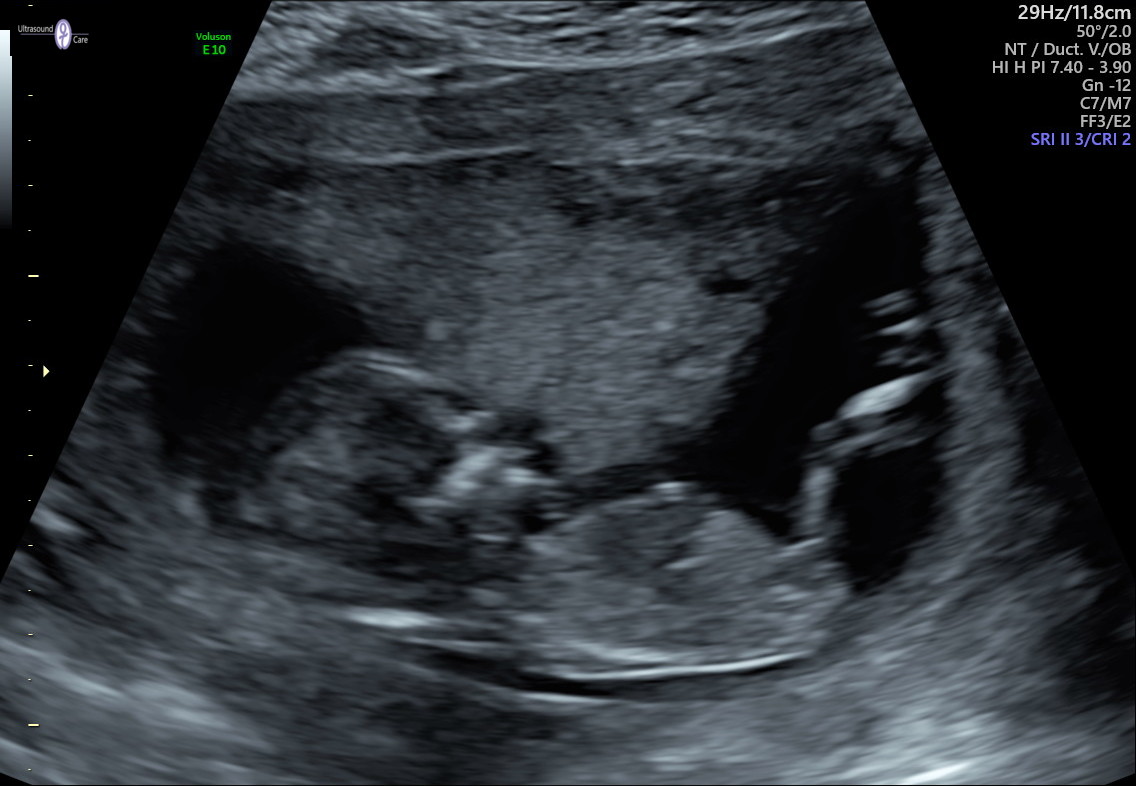

Ohhh I see what you mean, thanks Atomic! Had another ultrasound today at 14w4d, can you see anything more in this picture?

Attachment 43282